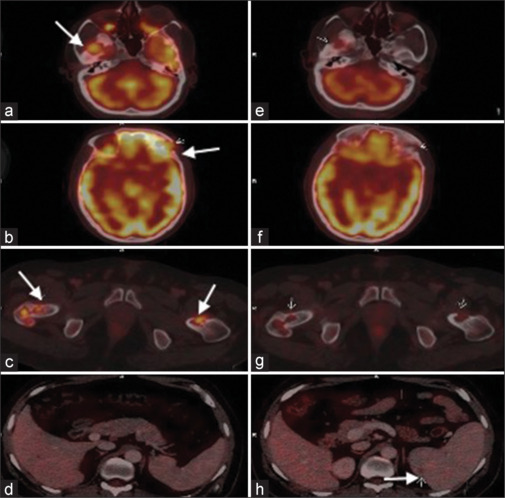

背景:朗格汉斯细胞组织细胞增多症(LCH)是一种罕见的血液系统疾病,由于其多样的临床表现,给诊断带来了重大挑战。本研究旨在分析F-18氟脱氧葡萄糖正电子发射断层扫描计算机断层扫描(F-18 FDG PET/CT)在LCH的诊断、分期和治疗中的应用。材料与方法:纳入59例LCH患者,共进行了93次F-18 FDG PET/CT扫描(包括19例随访扫描)。评估FDG摄取异常部位,并测量所有扫描的最大标准化摄取值。结果:单系统LCH 25例(42.4%),多系统累及LCH 34例(57.6%),49/59。LCH最常见的受累部位为骨骼(49/59,83.1%)和淋巴结(39/59,44.9%)。单发SS-LCH骨病变12/59(20.3%),以颅骨为主。其他常见受累部位包括肺、肝、脾、骨髓、皮肤和软组织。较不常见的受累部位包括胰腺(2例)、枕叶(1例)和肠(1例)。PET/CT用于19例患者的疗效评估,并帮助疾病进展(2例)和复发(2例)的患者启动二线化疗。7例临床怀疑为LCH,根据病变特征和FDG摄取情况诊断为LCH,并经活检证实。结论:F-18 FDG PET/CT显示了LCH病变的形态学和代谢特征,有助于准确诊断、评估疾病负担和预测预后,可作为LCH治疗的综合影像学工具。

Results: Twenty-five patients (42.4%) had single system LCH (SS-LCH) and 34 patients (57.6%) had multisystem involvement LCH, 49/59. The most common sites of LCH involvement were bones (49/59, 83.1%) and lymph nodes (39/59, 44.9%). 12/59 patients (20.3%) had unifocal SS-LCH bone lesions, mostly in skull. The other common sites involved were lungs, liver, spleen, marrow, skin, and soft tissues. Less commonly involved sites included pancreas (2 cases), occipital lobe (1 case), and bowel (1 case). PET/CT was used in response assessment in 19 patients and helped in initiation of second line chemotherapy in cases of disease progression (2 cases) and relapse (2 cases). Seven cases with clinical suspicion were diagnosed as LCH based on lesion characteristics and FDG uptake, which were later biopsy proven.